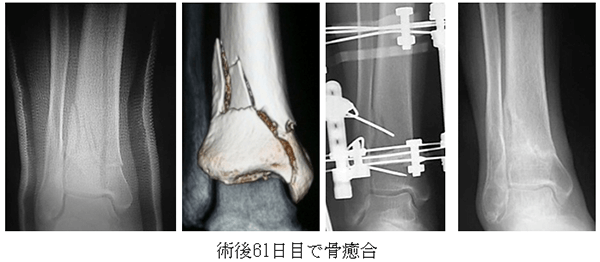

軟部組織損傷を伴う高齢者Pilon骨折に対するMATILDA法

高齢者の脛骨天蓋骨折は老人性皮膚萎縮のため軟部組織関連の合併症が多く、さらに関節内骨折のため早期荷重が困難です。AIMGではIlizarov創外固定によるロングロッドを用いた閉鎖的整復+外傷性関節症の進行抑制を目的としたDistraction arthroplastyを併用するMATILDA法(Multidirectional Ankle Traction using Ilizarov external fixator with Long rod and Distraction Arthroplasty of Pilon fracture)により良好な成績を修めています。

Ilizarov創外固定を可及的早期にはずすことができるように、AIMGではA-BONEと協同し、粉砕骨折に対する超音波骨癒合促進器と骨粗鬆症治療薬テリパラチドを併用するCELTAB法 (Combined Effect of Low-intensity pulsed ultrasound and Teriparatide in Acceleration of Bone healing)を早期骨癒合目的に行い、従来より大幅に抜釘時期を短縮しています。